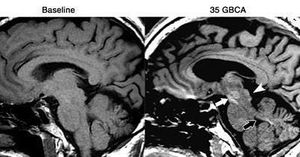

Fig. T1-weighted MRI of a 61-year-old man with left frontal glioblastoma shows high signal intensity in the colliculi (arrowhead), red nucleus and substantia nigra (white arrow), and superior cerebellar peduncle (black arrow) after 35 GBCA administrations, compared with baseline MRI prior to GBCA. Images courtesy of Radiology.